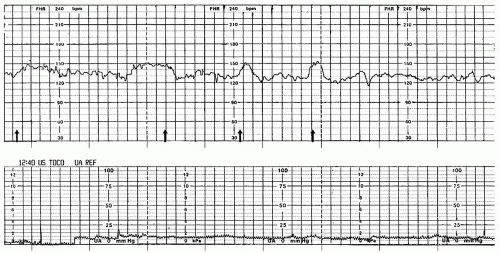

임신 31주에 접어든 34세의 미분만부가 갑작스러운 질출혈을 호소하며 병원을 방문했다. 혈압은 128/82 mmHg, 맥박은 78회/분, 호흡은 18회/분, 체온은 36.9°C로 측정되었다. 골반검사 결과 질 내에 축적된 혈액이 확인되었으나, 자궁경부에서의 추가적인 출혈은 관찰되지 않았다. 혈액검사 결과, 초음파 사진 및 전자태아심음감시장치 검사 결과이다. 적절한 처치는?

• 현재 자궁목이 닫혀있고 자궁수축이 없으며 산모의 V/S, lab 결과 모두 정상, FHR 또한 reactive하므로 산모와 태아 모두 안정적이다.

• 현재 임신 31주로, 즉각적 분만보다는 임신 유지의 이득이 더 크므로 close monitoring 하며 경과관찰한다.